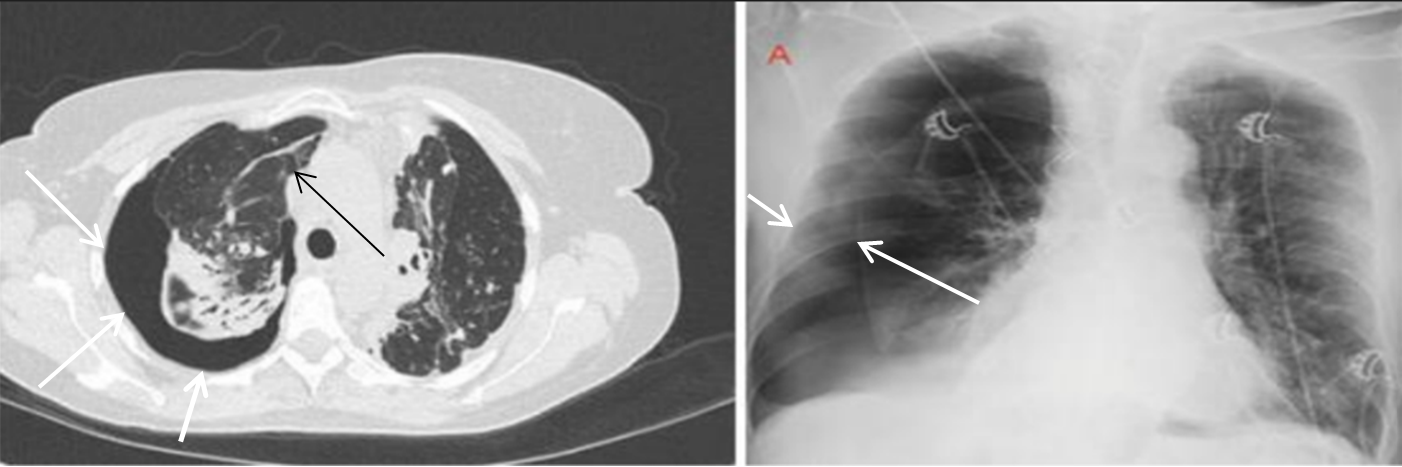

All patients presented with dyspnea and respiratory distress upon admission. A persistent air leak (PAL) lasting more than 72 hours following chest tube drainage prompted further evaluation. Chest computed tomography (CT) identified pulmonary bullae in all cases. The distribution of pulmonary bullae by anatomical location is detailed in Table 2, demonstrating that the right upper lobe was the most frequently involved site (58%). The mean bulla size ranged from 1.5 to 2.0 cm. Localized bullous lesions were identified in 33 patients, whereas 27 patients exhibited diffuse bullous disease. Among those with diffuse disease, 10 patients presented with bilateral involvement. (An illustrative example of right-sided SSP in a patient with COPD is provided in Figure 1.)

A 62-year-old man with right pneumothorax and combined pulmonary emphysema. Chest CT and X-ray images (August 2023) show right-sided SSP in a patient with COPD (white arrowheads), with a visible bullae in the right lung field (black arrowhead).